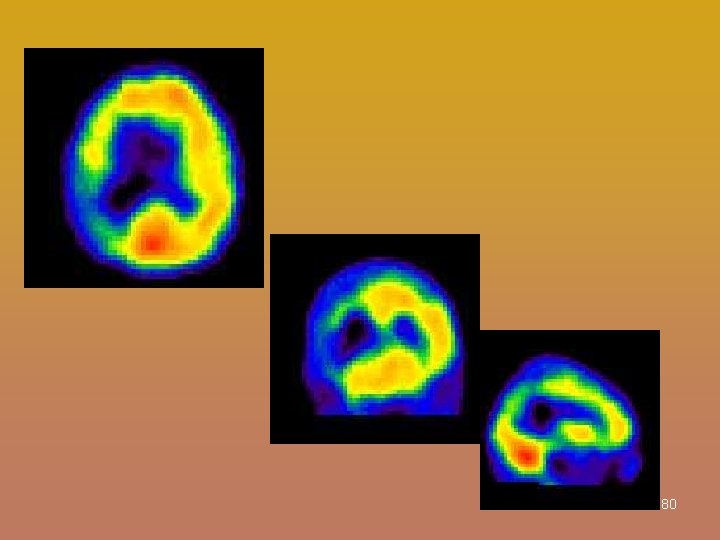

PET Scan & SPECT Scan • PET = Positron Emission Tomography • Single Photon Emission Computed Tomography 76

PET NUCLEAR MED + CT or MRI- co-registration 79

80